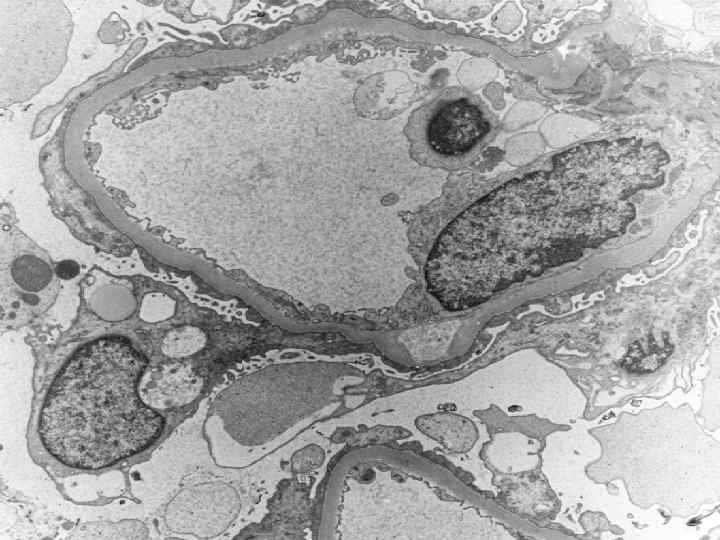

Исследование почечных биоптатов l Световая микроскопия l Иммунофлюоресцентная l Электронная

Минимальные изменения клубочков l l Выявляются лишь при электронной микроскопии Наблюдается чаще у детей l Характерен нефротический синдром с массивными отеками l Наиболее эффективны глюкокортикоиды l Прогноз достаточно благоприятный, ХПН развивается редко

Болезнь минимальных изменений